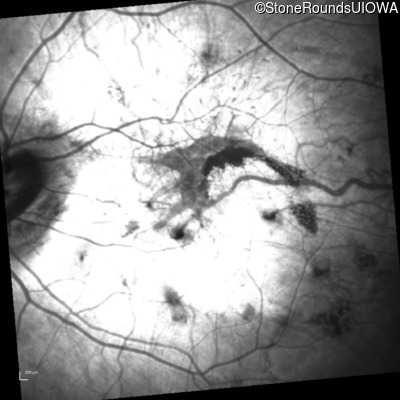

Infrared Fundus Photograph - Right - 20/40 -2

Exemplar